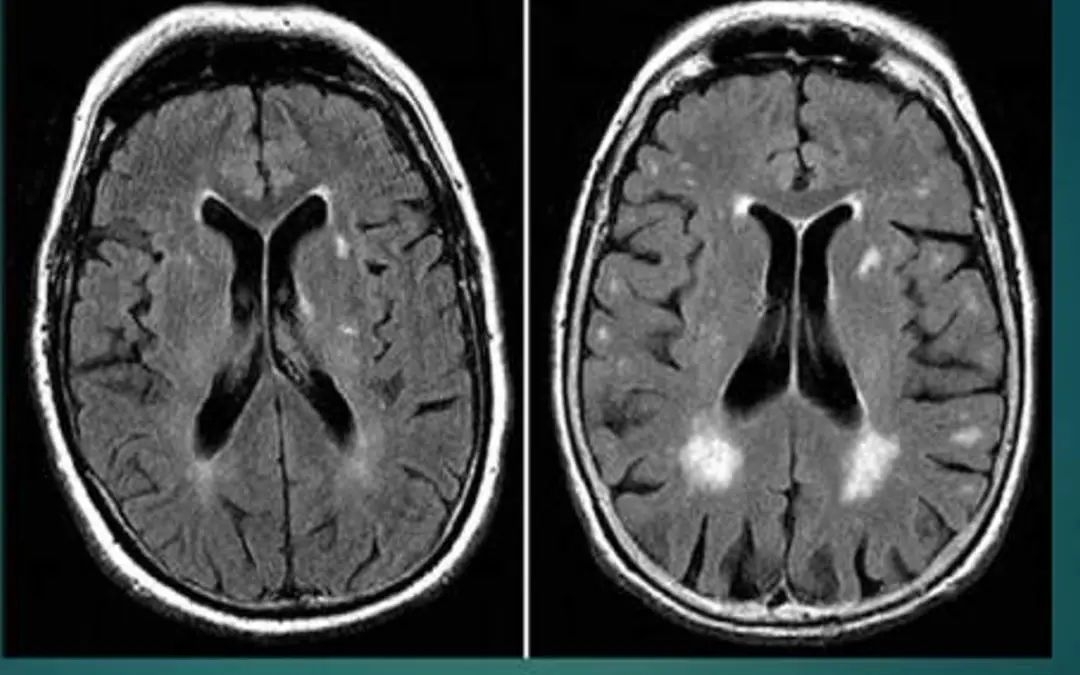

脑白质脱髓鞘

表现为皮层下白质及侧脑室周围多发点状或斑片状长Tl、长T2信号,可以与其他类型影像学损害并存。临床表现为精神障碍、行走困难、肌张力高、病理征阳性等。

此外,西班牙神经科学研究所,联合德国中央心理健康研究所的联合研究小组,将90名酗酒者的大脑磁共振成像,同36名不饮酒者进行对比分析,观察到了酗酒者大脑白质的持续退变过程。

酗酒者在清醒两周后(左)大脑中的电活动(蓝线)

明显少于禁酒者(右)

大脑扫描结果显示,酒精对两个大脑部位的影响最大,一个是海马体,另一个是前额皮质。记忆、情感、决策以及行为等均受这两个部位控制,因此上述功能会受到损伤。

与滴酒不沾相比,醒酒两周后,饮酒者大脑内神经元的电活动仍明显偏少,这种影响会在停止饮酒后持续6个星期。

研究员圣地亚哥·卡纳勒博士说:“该研究成果挑战了人们的传统看法。事实上,酒精对大脑的伤害远不止于宿醉的那个早上,在那之后的至少6周,大脑神经元的‘沟通交流’都在发生改变,神经信号传递持续受到限制。”